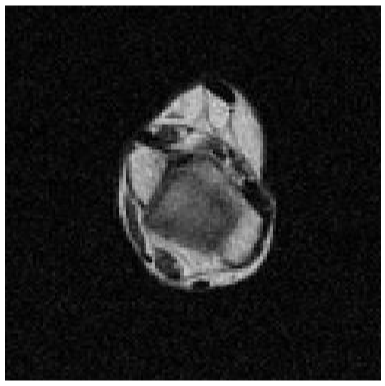

LOW-RES AXIAL HIP